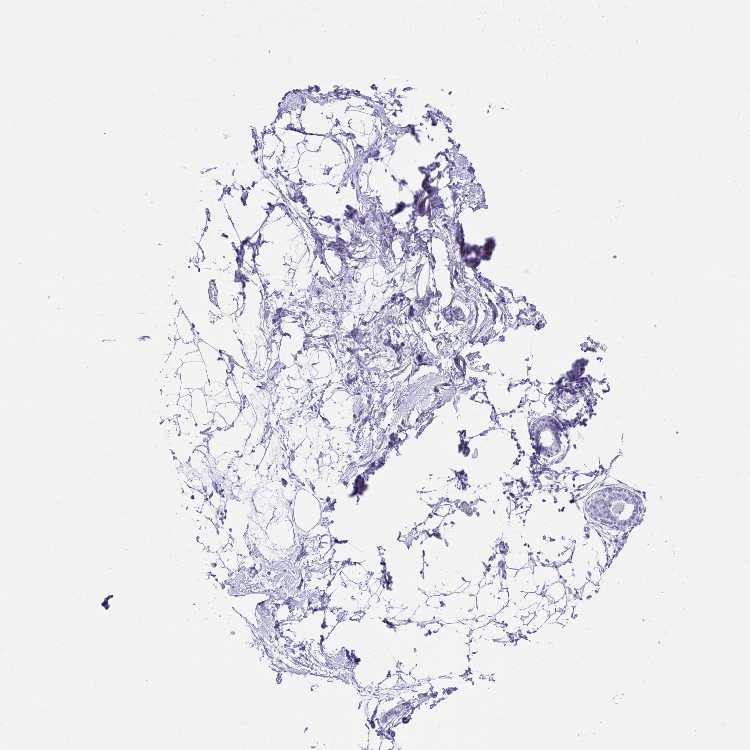

BREAST - Antibody stainingi

Antibody staining in the annotated cell types in the current human tissue is reported as not detected, low, medium, or high, based on conventional immunohistochemistry profiling in selected tissues. This score is based on the combination of the staining intensity and fraction of stained cells.

Each image is clickable and will lead to virtual microscopy that enables deeper exploration of all samples and also displays staining intensity scores, fraction scores and subcellular localization as well as patient and tissue information for each sample.

Antibody HPA056418

Adipocytes Not detected

Glandular cells Not detected

Myoepithelial cells Not detected